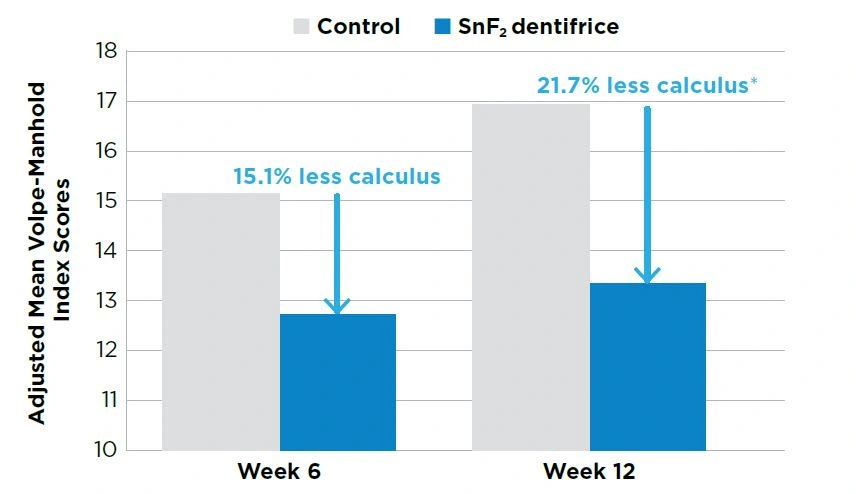

KEY CLINICAL FINDINGS

Subjects using the stabilized stannous fluoride (SnF22) dentifrice demonstrated 15.1% less calculus at Week 6 (P=0.05) and 21.7% less calculus at Month 3 (P<0.01) compared to subjects in the control group.

Both test products were well tolerated.

N=78. *Significant difference between groups (P<0.05) using analysis of covariance.

OBJECTIVE

To assess the calculus prevention benefit of an experimental stabilized SnF2 dentifrice relative to a negative control dentifrice.

STUDY DESIGN

This was a 3-month, parallel-group, double-blind, randomized and controlled clinical trial.

Subjects received a dental prophylaxis and then entered a 2-month run-in phase. At the end of 2 months, subjects received a Volpe-Manhold Index (V-MI) calculus examination.

Qualified subjects who formed a minimum of 9 mm of calculus on the lingual surfaces of the six mandibular anterior teeth received another prophylaxis and were randomly assigned to one of the two treatments:

- Experimental 0.454% stabilized SnF2 dentifrice (Crest® PRO-HEALTH™ Clean Mint [Smooth Formula], Procter & Gamble) with zinc to control calculus; or

- Negative control dentifrice (Colgate® Cavity Protection, Colgate-Palmolive).

Subjects brushed with their assigned product twice daily using a standard manual toothbrush, one minute per brushing, during the 3-month trial.

Safety and calculus measurements were taken via Oral Soft Tissue and Volpe-Manhold Index examinations at Baseline, Week 6 and Month 3..

Treatment groups were compared using analysis of covariance. All statistical tests were two-sided with a 5% level of significance.

CLINICAL COMMENT

Calculus build-up can lead to less efficient oral hygiene and tooth discoloration, as well as extending the time required for a dental prophylaxis. This research demonstrated a directional anti-calculus benefit for the SnF2 dentifrice relative to the control dentifrice in as early as 6 weeks. The relative benefit for the SnF2 dentifrice was even greater after 12 weeks of use. Dental professionals should consider recommending the SnF2 dentifrice for patients who form calculus, as it also improves gingival health and strengthens enamel.